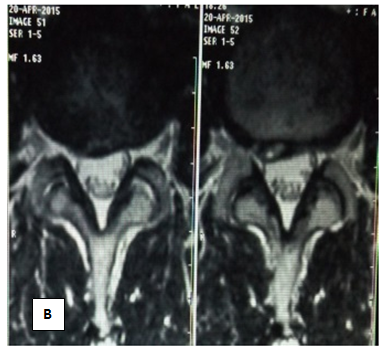

In the period from May to June 2015, patient S. was given a course of MFVVT from 15 procedures. During the first week, the patient's condition stabilized, pain and irradiation in the limb decreased, antalgic scoliosis is not detected, a symptom of tension of 50 degrees. By the end of the course of treatment, the patient's condition is good, there is no pain in the lower back. Preserve the area of ​​numbness in the left foot. Inspection after 2 months did not reveal pathological abnormalities. MRI from 27.08.15. (Figures 4A & 4B). Drive L 4-5: moderate decrease in disc height and intensity MR - signal. Op. posterior protrusion of the disc up to 4mm. Bone swelling of adjacent vertebrae.

Figure 4 Patient S. After the course of MFUVT.